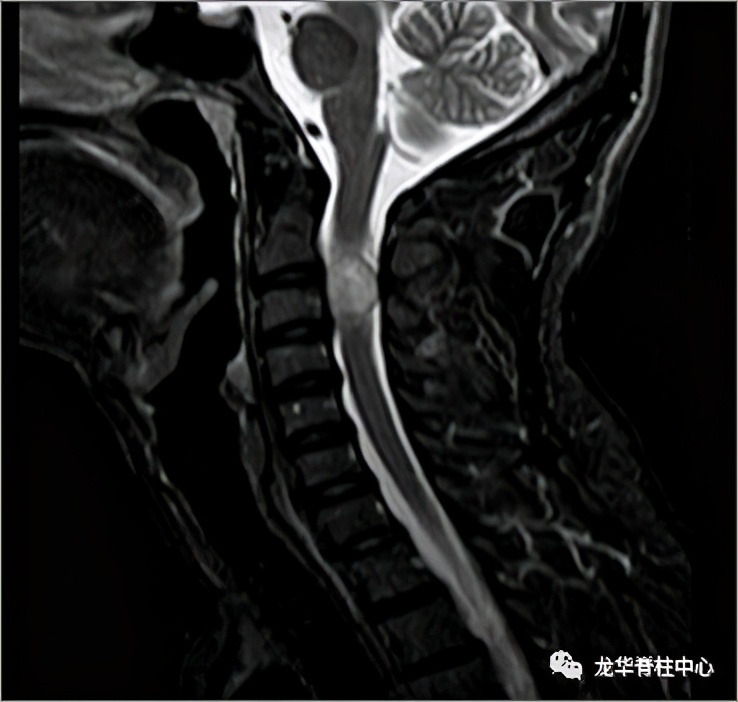

显微镜下寰枢椎脱位经口松解、后路固定术

开展深圳市首例寰枢椎脱位经口咽松解、后路椎弓根钉板内固定术